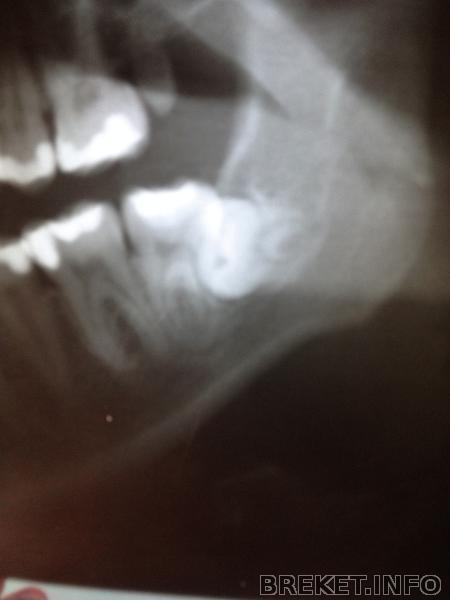

зубки сфотографирую, что бы достать нижнюю 8ку нужно вскрыть слизистую ,причем ее большую часть с вырываемой стороны, это все будет проходить через 7ку, затем нужно выпилить приличный кусок надкостницы , достать эту 8ку не повредив 7ку , ну и потом зашивать, но это все может приобрести обостренный характер...могут быть осложнения..и нервы задеть могут...в общем беда) Спасибо за советы! снимок направлю Андреищеву )

Сочувствую. У вас нижний левый зуб, как у меня верхний правый - растет в 7 так, что надо или сначала 7 удалять потом 8, или разворотить полчелюсти((( Попробуйте обсудить с ортом возможность удаления 5к и стягивания на их место 6 и 7 (в данном случае 8 поспособствуют перемещению этих "тугих" зубов"), тогда и место получите, и 8 может вылезут...

Посмотри на мою восьмерку, она лежала как раз в точно таком же положении, как у тебя (упиралась в 7-ку).

Горизонтальный зуб удалялся конечно посложнее ( можешь подробнее почитать в моем дневнике), но реабилитация, на удивление, проходила легче. 7-ку мне не удаляли и полчелюсти не разворотили))